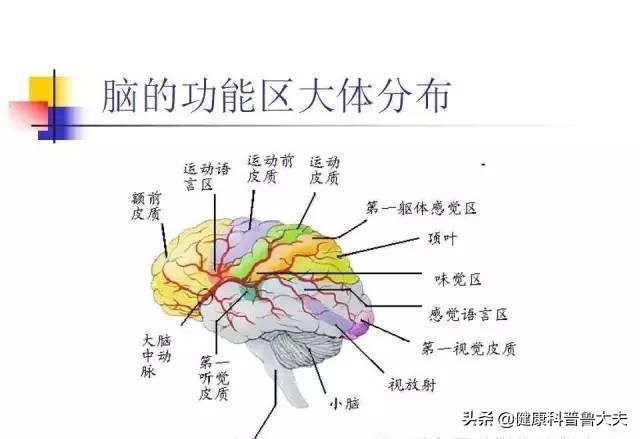

Notre cerveau gère presque toutes les fonctions de notre corps et est connu comme le commandant du corps. Le cerveau dépend du sang pour transporter l'oxygène et les nutriments dont il a besoin. Lorsque les vaisseaux sanguins sont bloqués pour diverses raisons, le cerveau est incapable d'obtenir de l'oxygène et des nutriments et meurt, entraînant la perte de fonctions de notre corps, ce qui est appelé infarctus cérébral. Les fonctions des différentes parties du cerveau étant différentes, les patients auront des séquelles plus ou moins importantes selon la localisation et l'étendue de la nécrose. Certaines personnes peuvent n'avoir qu'un léger vertige et découvrir qu'elles ont subi un infarctus cérébral lorsqu'elles se rendent à l'hôpital pour un examen (la plupart des patients atteints d'infarctus cérébral lacunaire sont découverts au cours de l'examen). Certains patients garderont des séquelles telles que l'hémiplégie, l'immobilité, la cécité, le retard mental, voire la mort.

Symptômes associés à un infarctus cérébral léger

Notre cerveau et les vaisseaux sanguins cérébraux sont un système très complexe, il y a de grandes artères, de petites artères, des artères pénétrantes, des artères basilaires, certains vaisseaux sanguins appartiennent aux vaisseaux de la circulation antérieure, d'autres aux vaisseaux de la circulation postérieure, selon les différentes parties du vaisseau sanguin infarci, la formation du cerveau de l'impact sur la santé est également différente, et les symptômes associés sont également différents, généralement dit, si le problème de l'infarctus cérébral n'est pas trop grave, en raison du site d'obstruction, de l'obstruction D'une manière générale, s'il s'agit d'un problème moins grave d'infarctus cérébral, en raison des différents sites de blocage, des degrés de blocage et des parties du cerveau touchées, les personnes atteintes d'infarctus cérébral peuvent présenter les symptômes suivants -

- Si la partie du blocage vasculaire cérébral affecte la partie du cerveau qui dirige les mouvements du corps, des symptômes tels que l'hémiplégie, l'ataxie, l'incapacité à marcher en ligne droite et la susceptibilité aux chutes peuvent apparaître.

- Si les vaisseaux sanguins cérébraux sont embolisés, ce qui affecte l'irrigation sanguine du cerveau, certains patients peuvent également souffrir de vertiges, de maux de tête, voire de nausées et de vomissements, et d'autres peuvent présenter des symptômes tels que des pertes de connaissance passagères.

- Si le blocage vasculaire cérébral affecte les zones fonctionnelles du cerveau dans le domaine de la déglutition et de la vocalisation, les personnes souffrant d'un infarctus cérébral léger ont tendance à souffrir d'aphasie, de dysphonie, de dysphagie, de paralysie faciale, et lorsque cela se produit, cela s'accompagne souvent de troubles légers des mouvements de la main, tels qu'une légère faiblesse de la main et des troubles de la motricité fine.

- Si l'obstruction des vaisseaux sanguins cérébraux affecte la zone du cerveau responsable de la sensation, des symptômes en termes de déficience sensorielle ou d'anomalie sensorielle, tels que l'engourdissement des membres asymétriques dans la moitié du corps et la perte de la sensation de douleur et de température, peuvent survenir.

- Si l'obstruction des vaisseaux sanguins cérébraux affecte le nerf central de la vision, elle peut provoquer des anomalies visuelles, notamment une vision anormale, des hallucinations visuelles, voire une incapacité à voir et des troubles des mouvements oculaires.

Examinons tout d'abord le terme "infarctus cérébral léger". En général, si l'on classe le degré de la maladie, on trouve les expressions "léger", "modéré" ou "grave", et avec l'infarctus cérébral, cela signifie que le degré de l'infarctus cérébral est relativement faible. L'infarctus cérébral est le nom abrégé de la maladie "infarctus cérébral" ou "infarctus cérébral", l'infarctus cérébral et l'infarctus cérébral sont des noms différents de la même maladie, seuls les grands et les petits noms sont différents. L'infarctus cérébral est l'infarctus des cellules cérébrales, la signification de la mort des cellules cérébrales, les cellules cérébrales sont l'unité de base du tissu cérébral, le tissu cérébral est divisé en cerveau, mésencéphale, cervelet, tronc cérébral.

Chaque tissu cérébral et chaque zone fonctionnelle sont différents, tout comme le rôle qu'ils jouent.

Par exemple, l'hémisphère gauche du cerveau régit les mouvements du côté droit du corps et l'hémisphère droit contrôle les mouvements du côté gauche du corps ; le lobe préfrontal du cerveau est responsable de la pensée, de la planification et est associé aux besoins et aux émotions de l'individu. Le lobe pariétal du cerveau - répond aux sensations de douleur, de toucher, de goût, de température, de pression ; cette zone est également associée aux mathématiques et à la logique. Lobe temporal du cerveau - Responsable du traitement des informations auditives, il est également associé à la mémoire et aux émotions. Lobe occipital du cerveau - Responsable du traitement des informations visuelles. Le système limbique du cerveau est impliqué dans la mémoire et dans les aspects comportementaux et émotionnels. Il est impliqué dans tous les aspects du corps humain tels que les sensations, les mouvements, les émotions et la mémoire.

Par exemple, la fonction du cervelet est étroitement liée à la fonction d'équilibre du corps. La fonction du tronc cérébral est principalement de maintenir la vie de l'individu, y compris le rythme cardiaque, la respiration, la digestion et d'autres fonctions physiologiques importantes.

Chaque partie du tissu cérébral a donc une fonction différente des cellules cérébrales. Si des cellules cérébrales meurent dans cette partie, la fonction de cette partie est diminuée ou perdue. Par diminution, on entend que la zone de mort cellulaire est plus petite, et par perte, on entend que la zone de mort cellulaire est plus grande.